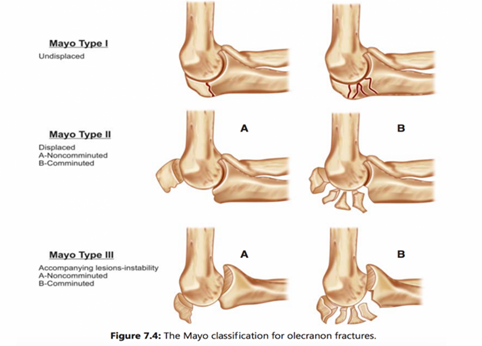

Là gãy đầu trên xương trụ cùng với mỏm vẹt.Thường do một chấn thương mạnh ngã đập khuỷu. Do là chỗ bám cơ tam đầu nên thường di lệch, gãy nội khớp nên ảnh hưởng tới vận động gấp duỗi khuỷu.

X-Quang: Xác định được đặc điểm ổ gãy

Điều trị phẫu thuật kết hợp gãy mỏm khuỷu:

- Phẫu thuật kết hợp khớp khủy tay được chỉ định cho gãy di lệch nhiều, gãy hở.

- Phương tiện được sử dụng để kết hợp xương là: Đinh và chỉ thép hoặc nẹp vít.